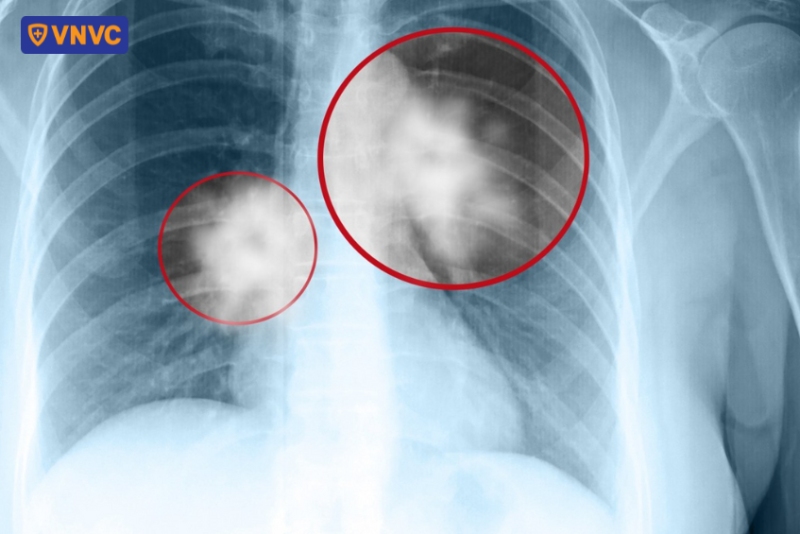

Xạ hình phổi (chụp xạ hình V/Q) là kỹ thuật chẩn đoán hình ảnh y học hạt nhân, sử dụng một lượng nhỏ chất phóng xạ để đánh giá chức năng thông khí (lưu thông không khí) và sự phân bố lưu lượng máu (lưu thông máu) trong phổi.

Công dụng chính của chụp xạ hình V/Q là chẩn đoán xác định các cục máu đông trong phổi, giúp Bác sĩ đưa ra quyết định lâm sàng thông qua đánh giá các hình ảnh cho thấy sự thông khí và tưới máu ở tất cả các vùng của phổi. (1)